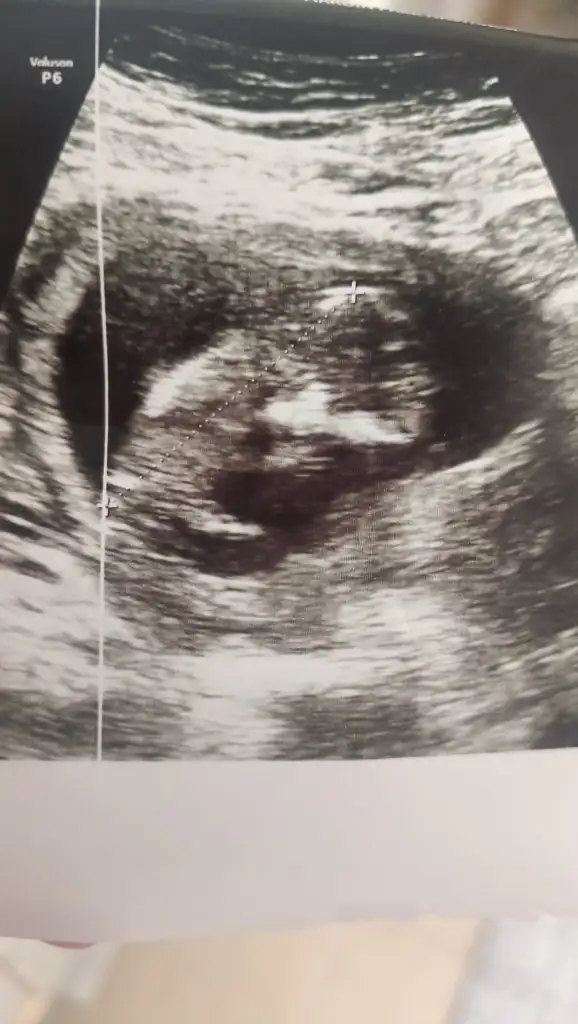

MaşallahKızlar merhaba 12 haftalık gebeyim tahminde bulunur musunuz?Eki Görüntüle 3409507

Kızlar merhaba 12 haftalık gebeyim tahminde bulunur musunuz?er

Erkeğe benzettimKızlar merhaba 12 haftalık gebeyim tahminde bulunur musunuz?Eki Görüntüle 3409507

Usg kalitesi de iyi olmayabilir ben kıza benzettim . Erkek bebekler çünkü çok net oluyor iskelet yapısı daha belirgin onlardaKızlar merhaba 12 haftalık gebeyim tahminde bulunur musunuz?Eki Görüntüle 3409507